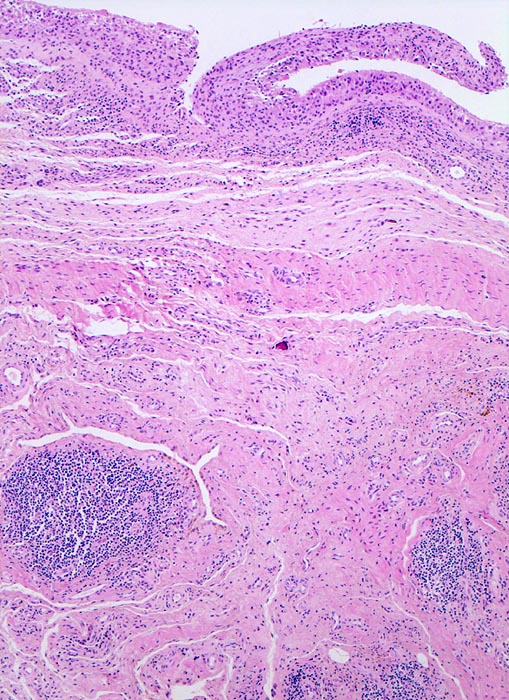

PathoPic ID 4773 - Synovialitis bei chronischer Polyarthritis

Synovialitis bei chronischer Polyarthritis

Systemerkrankung/Immunpathologie

Synovialis

Knochen, Knorpel, Gelenke

Verdickte synoviale

Deckzellschicht.

Lymphofollikuläre Entzündungsinfiltrate im Stroma.

Bekannte seropositive chronische Polyarthritis.

Der Nachweis von Lymphfollikeln ist typisch, aber nicht beweisend für eine chronische Polyarthritis.

Histologie

50